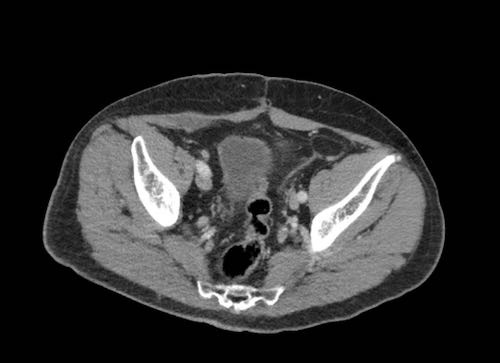

Ca lâm sàng 2

Cuộn qua các lát cắt.

Bạn có thể phát hiện tất cả các tổn thương cấy ghép phúc mạc không?